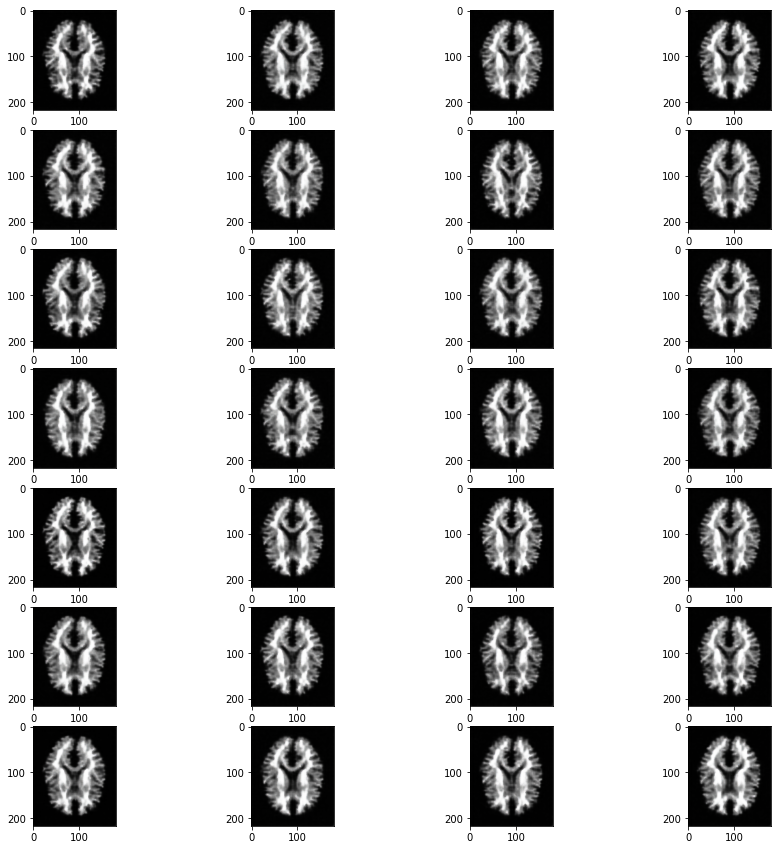

One of the main aspects of our project is MRI Image Synthesis. In this, we convert T1-Weighted images into T2-Weighted images. Along with this, our other model helps by generating Segmented Brain MRI images to show the distribution of white matter.

So we have created two models, one for Image synthesis and the other does Segmentation. Both works on generating images. We have implemented VAEs to achieve the purpose.